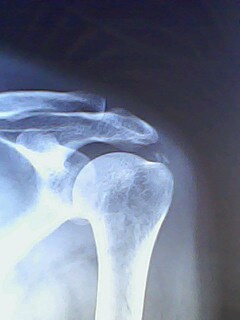

前几天有一个病人因肩痛在别处行针灸治疗,针灸一次后痛点上移至肩关节岗上肌处,并且疼痛加剧彻夜难眠。前天到县医院检查拍了片子,说是肩关节处长骨头需手术治疗。病人不放心今天又到市医院重新检查拍了片子说是岗上肌机化需要封闭治疗。